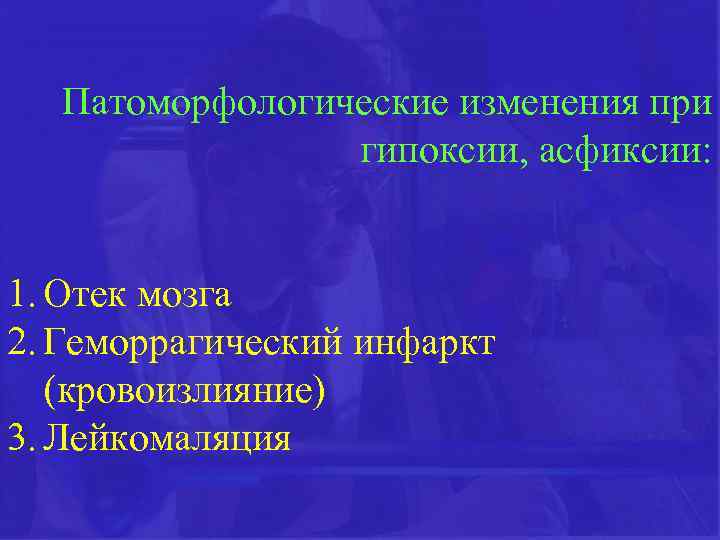

Патоморфологические изменения при гипоксии, асфиксии: 1. Отек мозга 2. Геморрагический инфаркт (кровоизлияние) 3. Лейкомаляция

Патоморфологические изменения при гипоксии, асфиксии: 1. Отек мозга 2. Геморрагический инфаркт (кровоизлияние) 3. Лейкомаляция